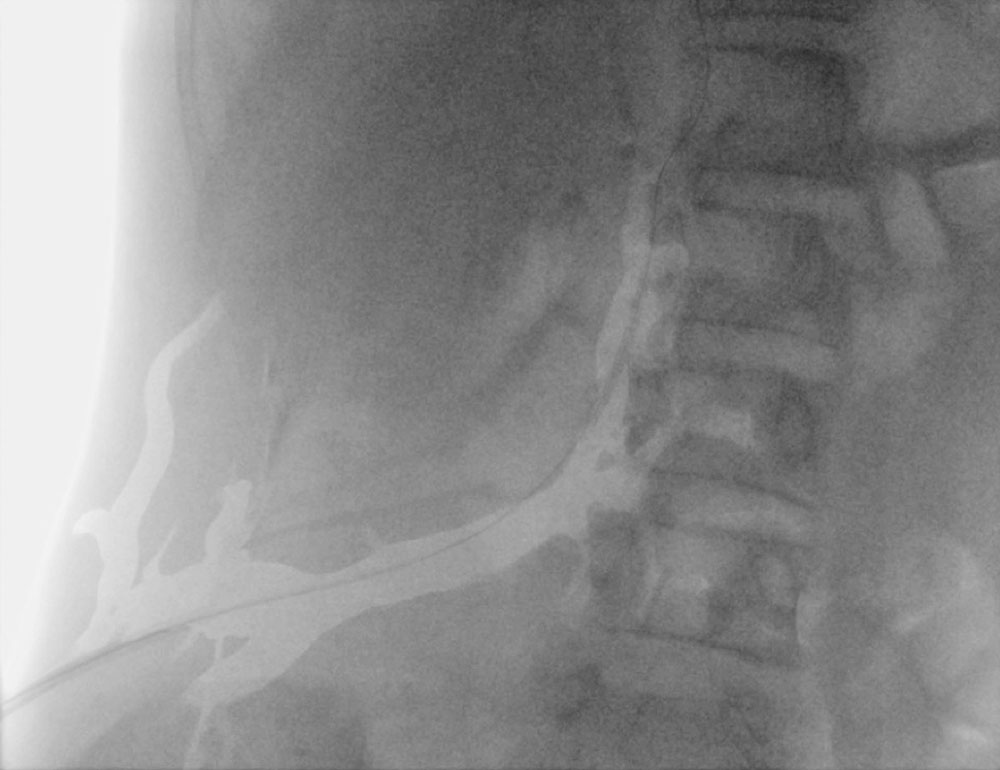

Gefäßmalformationen können Kapillaren (KM), Venen (VM) und/oder Lymphgefäße (LM) betreffen, weiterhin können seltener auch arteriovenöse Malformationen (AVM) auftreten. Charakteristisch sind kapilläre Malformationen (anfangs häufig purpurfarben, später abblassend) im Bereich des Rumpfes. Die venöse Malformation führt oft zu großen Marginalvenen, die bis in den Thorax reichen können. Die arteriovenösen Malformationen befinden sich häufig in der Nähe der lipomatösen Massen oder durchsetzen diese; auch gibt es sie gehäuft paraspinal.